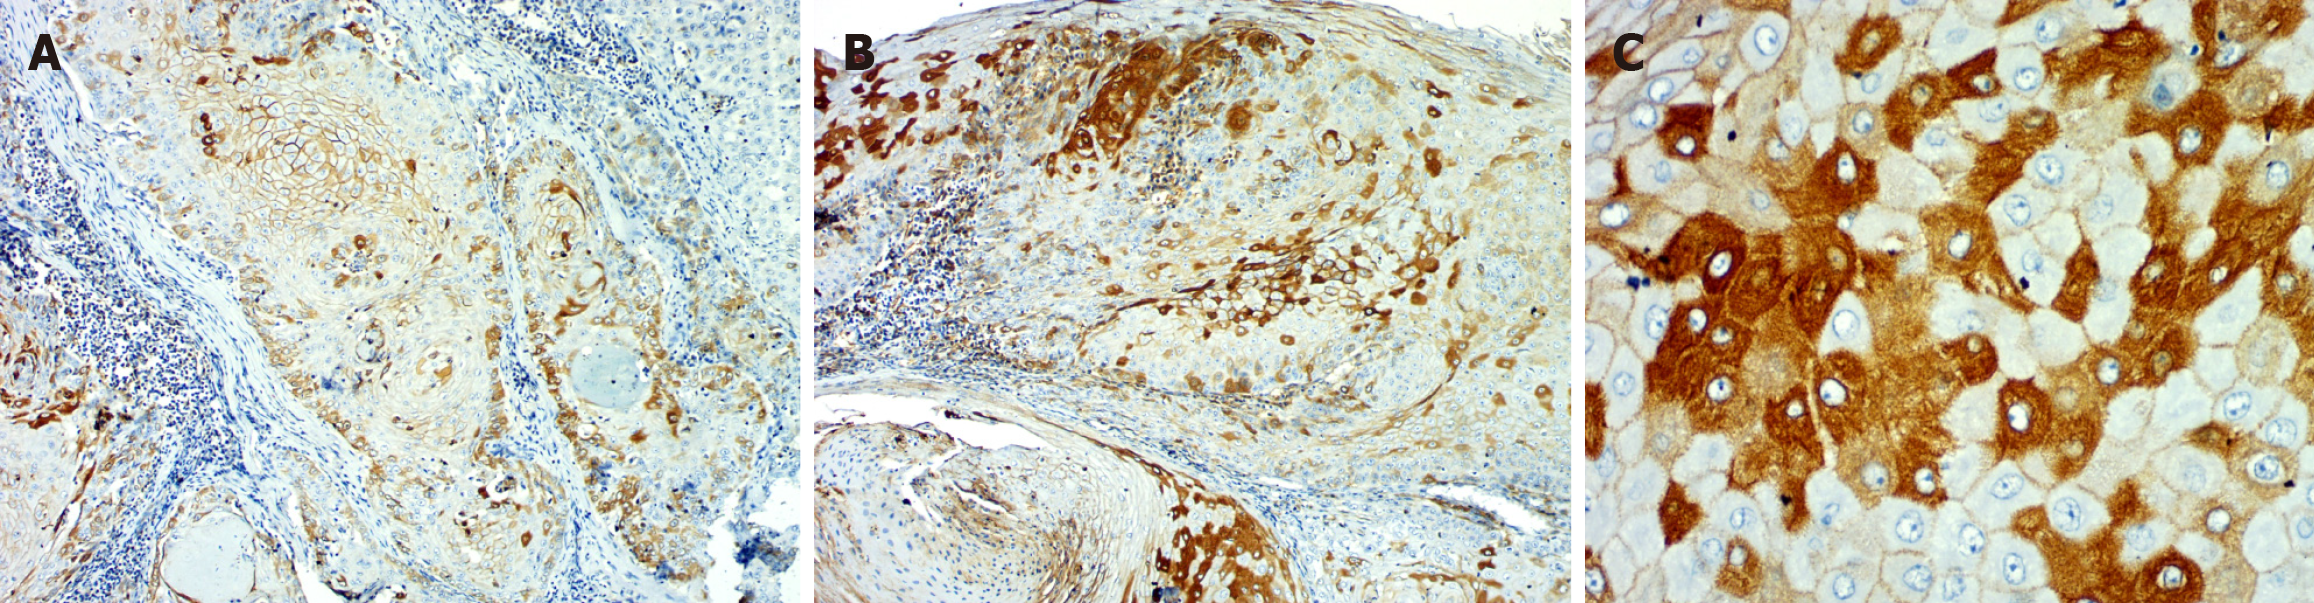

Percentage: In the OED, the majority of cases (n = 24) exhibited over 50% positivity for E-cadherin, whereas in OSCC, 15 cases shown over 50%, 9 instances displayed 25%-50%, and 5 cases indicated 1%-25% positivity. There was a significant reduction in the percentage of positivity of E-cadherin expression in OSCC as compared to OED (P = 0.0315) (Table 1, Figures 1 and 2).

Percentage: Eighteen OED cases had > 50% ZEB 1 positivity in the epithelium, ten had 25%-50% positivity, and two had 1%-25%. In OSCC, the majority of the cases (n = 23) showed > 50%, 6 cases 25%-50%, and 1 case 1%-25% positivity. Overall, the percentage of positivity from OED to OSCC increased significantly in both groups (Table 2, Figures 1 and 3).

The OED group observed a decrease in intensity and positive% from mild to moderate to severe dysplasia. A switch in location of E-cadherin from membrane to cytoplasmic expression was noted, which was consistent with previous research[29-31]. In advanced OED, the loss of cell adhesion mediated by E-cadherin is correlated to the loss of epithelial architecture[29-31]. Its participation in beta-catenin activation and nuclear translocation could explain its change from membrane to cytoplasmic expression. This will activate signaling pathways such as the Wnt pathway, which will enhance the malignant potential in OED[29-31].

In OSCC, there was a considerable decrease in intensity and proportion of positivity and a shift from membrane to cytoplasmic location consistent with findings from literature[32]. Loss of differentiation and higher grades presented a decrease in E-cadherin expression, which is in line with histological observations of epithelial phenotypic loss. Reduced E-cadherin expression is therefore crucial for the change of OED to OSCC[32]. In OSCC, changes in E-cadherin expression are related to the development of an invasive phenotype and a poor clinical outcome[33].

The intensity and percentage of ZEB1 positivity increased in OED epithelium with the increase in grade of dysplasia. This finding is similar to the research done by Ahmed et al[35] in 2017. The expression of ZEB1 was in the basal layer in moderate and severe dysplasia, as well as some cytosolic expression in the spinous layer. The most plausible explanation for such an increase in expression and shift into the cytoplasm is its function in activating target genes involved in gaining the mesenchymal phenotype and promoting malignant transformation.

In OSCC, ZEB1 expression exhibited higher intensity and percentage of positive cells as well as predominant cytoplasmic expression. ZEB1 switches from a predominantly nuclear subcellular site in dysplasia to a heavily cytosolic subcellular location in cancer. Experiments have shown that phosphorylation of ZEB1 by particular kinase pathways causes cytosolic localization[35,36]. Changes in the cancer cells' surrounding environment may be causing this alteration in signaling. ZEB-1 activates mesenchymal differentiation target genes via interacting with the acetyltransferases p300/p300/CBP-associated factor and SMADs[36]. Increased ZEB-1 expression is associated with a worse overall survival rate and recurrence in colorectal, esophageal squamous cell, pancreatic, gastric, and hepatocellular cancers[35]. According to Ahmed et al[35], the presence of ZEB1 in the cytosol of certain cells indicates a molecular mechanism for subcellular distribution regulation. SNAIL and TWIST, two functionally related EMT-transcription factors, are regulated in part by phosphorylation, which affects nuclear localization directly[36].